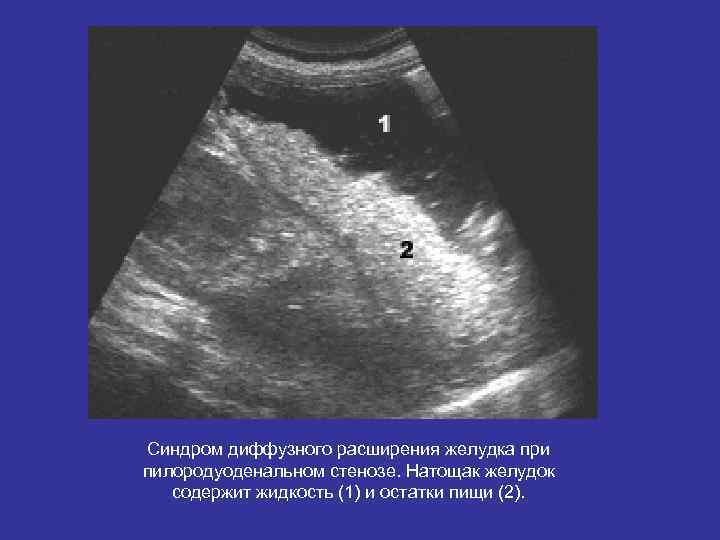

Синдром диффузного расширения желудка при пилородуоденальном стенозе. Натощак желудок содержит жидкость (1) и остатки пищи (2).